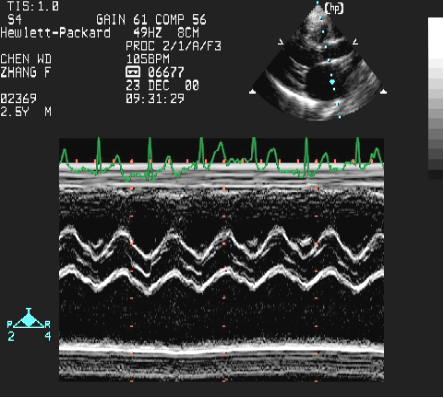

室间隔缺损:超声心动图表现

左房增大 左室增大

(室间隔缺损的间接征象)